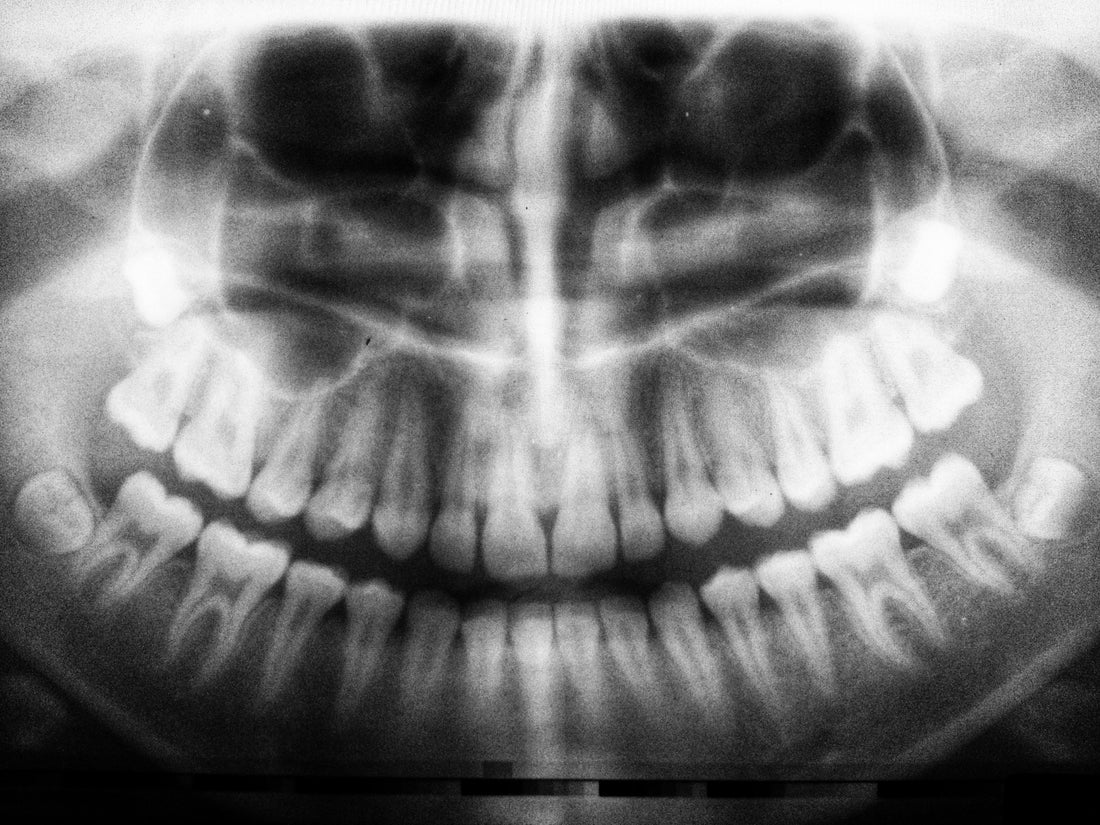

Does Sucralose Rot Your Teeth?

One of the major concerns regarding sucralose is whether it can lead to tooth decay and cavities. So, does sucralose rot your teeth? Sucralose itself is non-fermentable, meaning oral bacteria cannot readily metabolize it to produce harmful acids that damage tooth enamel.

However, many products that contain sucralose also have other ingredients, such as acids or preservatives, that can contribute to tooth damage. In fact, some of the ingredients in diet sodas and low-sugar drinks can do more damage to your teeth than sugar itself.